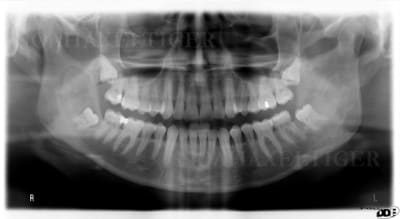

Extraction en 2004

La patiente ne revient pas après, pano demandé par un confrère en 2007 mais la patiente ne retourne pas le voir

Cadeau cette année elle vient pour faire finir 47

Pano demandé